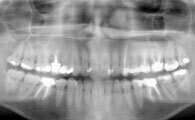

Une radio panoramique dentaire est un cliché de l'ensemble de la denture et des articulations temporo-mandibulaires.